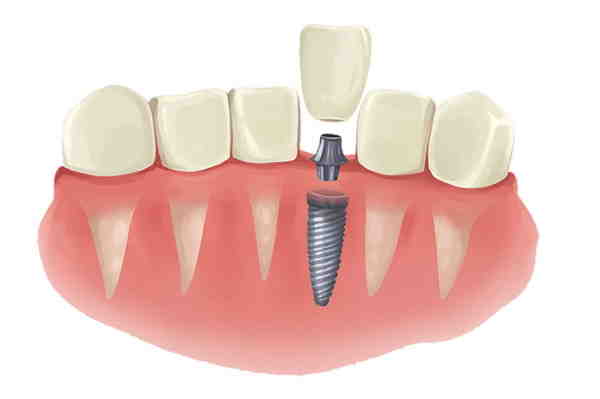

What are dental implants

So, is dental surgery worth all the trouble? Because of their durability, appearance, and function, dental implants are the best option for missing missing teeth, giving you a long-term option that can last a lifetime.

Generally, intoxicants are accepted as a better option than crowns if you have the money you can afford. Dental implants do not affect the surrounding teeth, and offer a lower risk of infection. However, as shown, there are many benefits to crowns, and in fact, both are used to address slightly different issues.